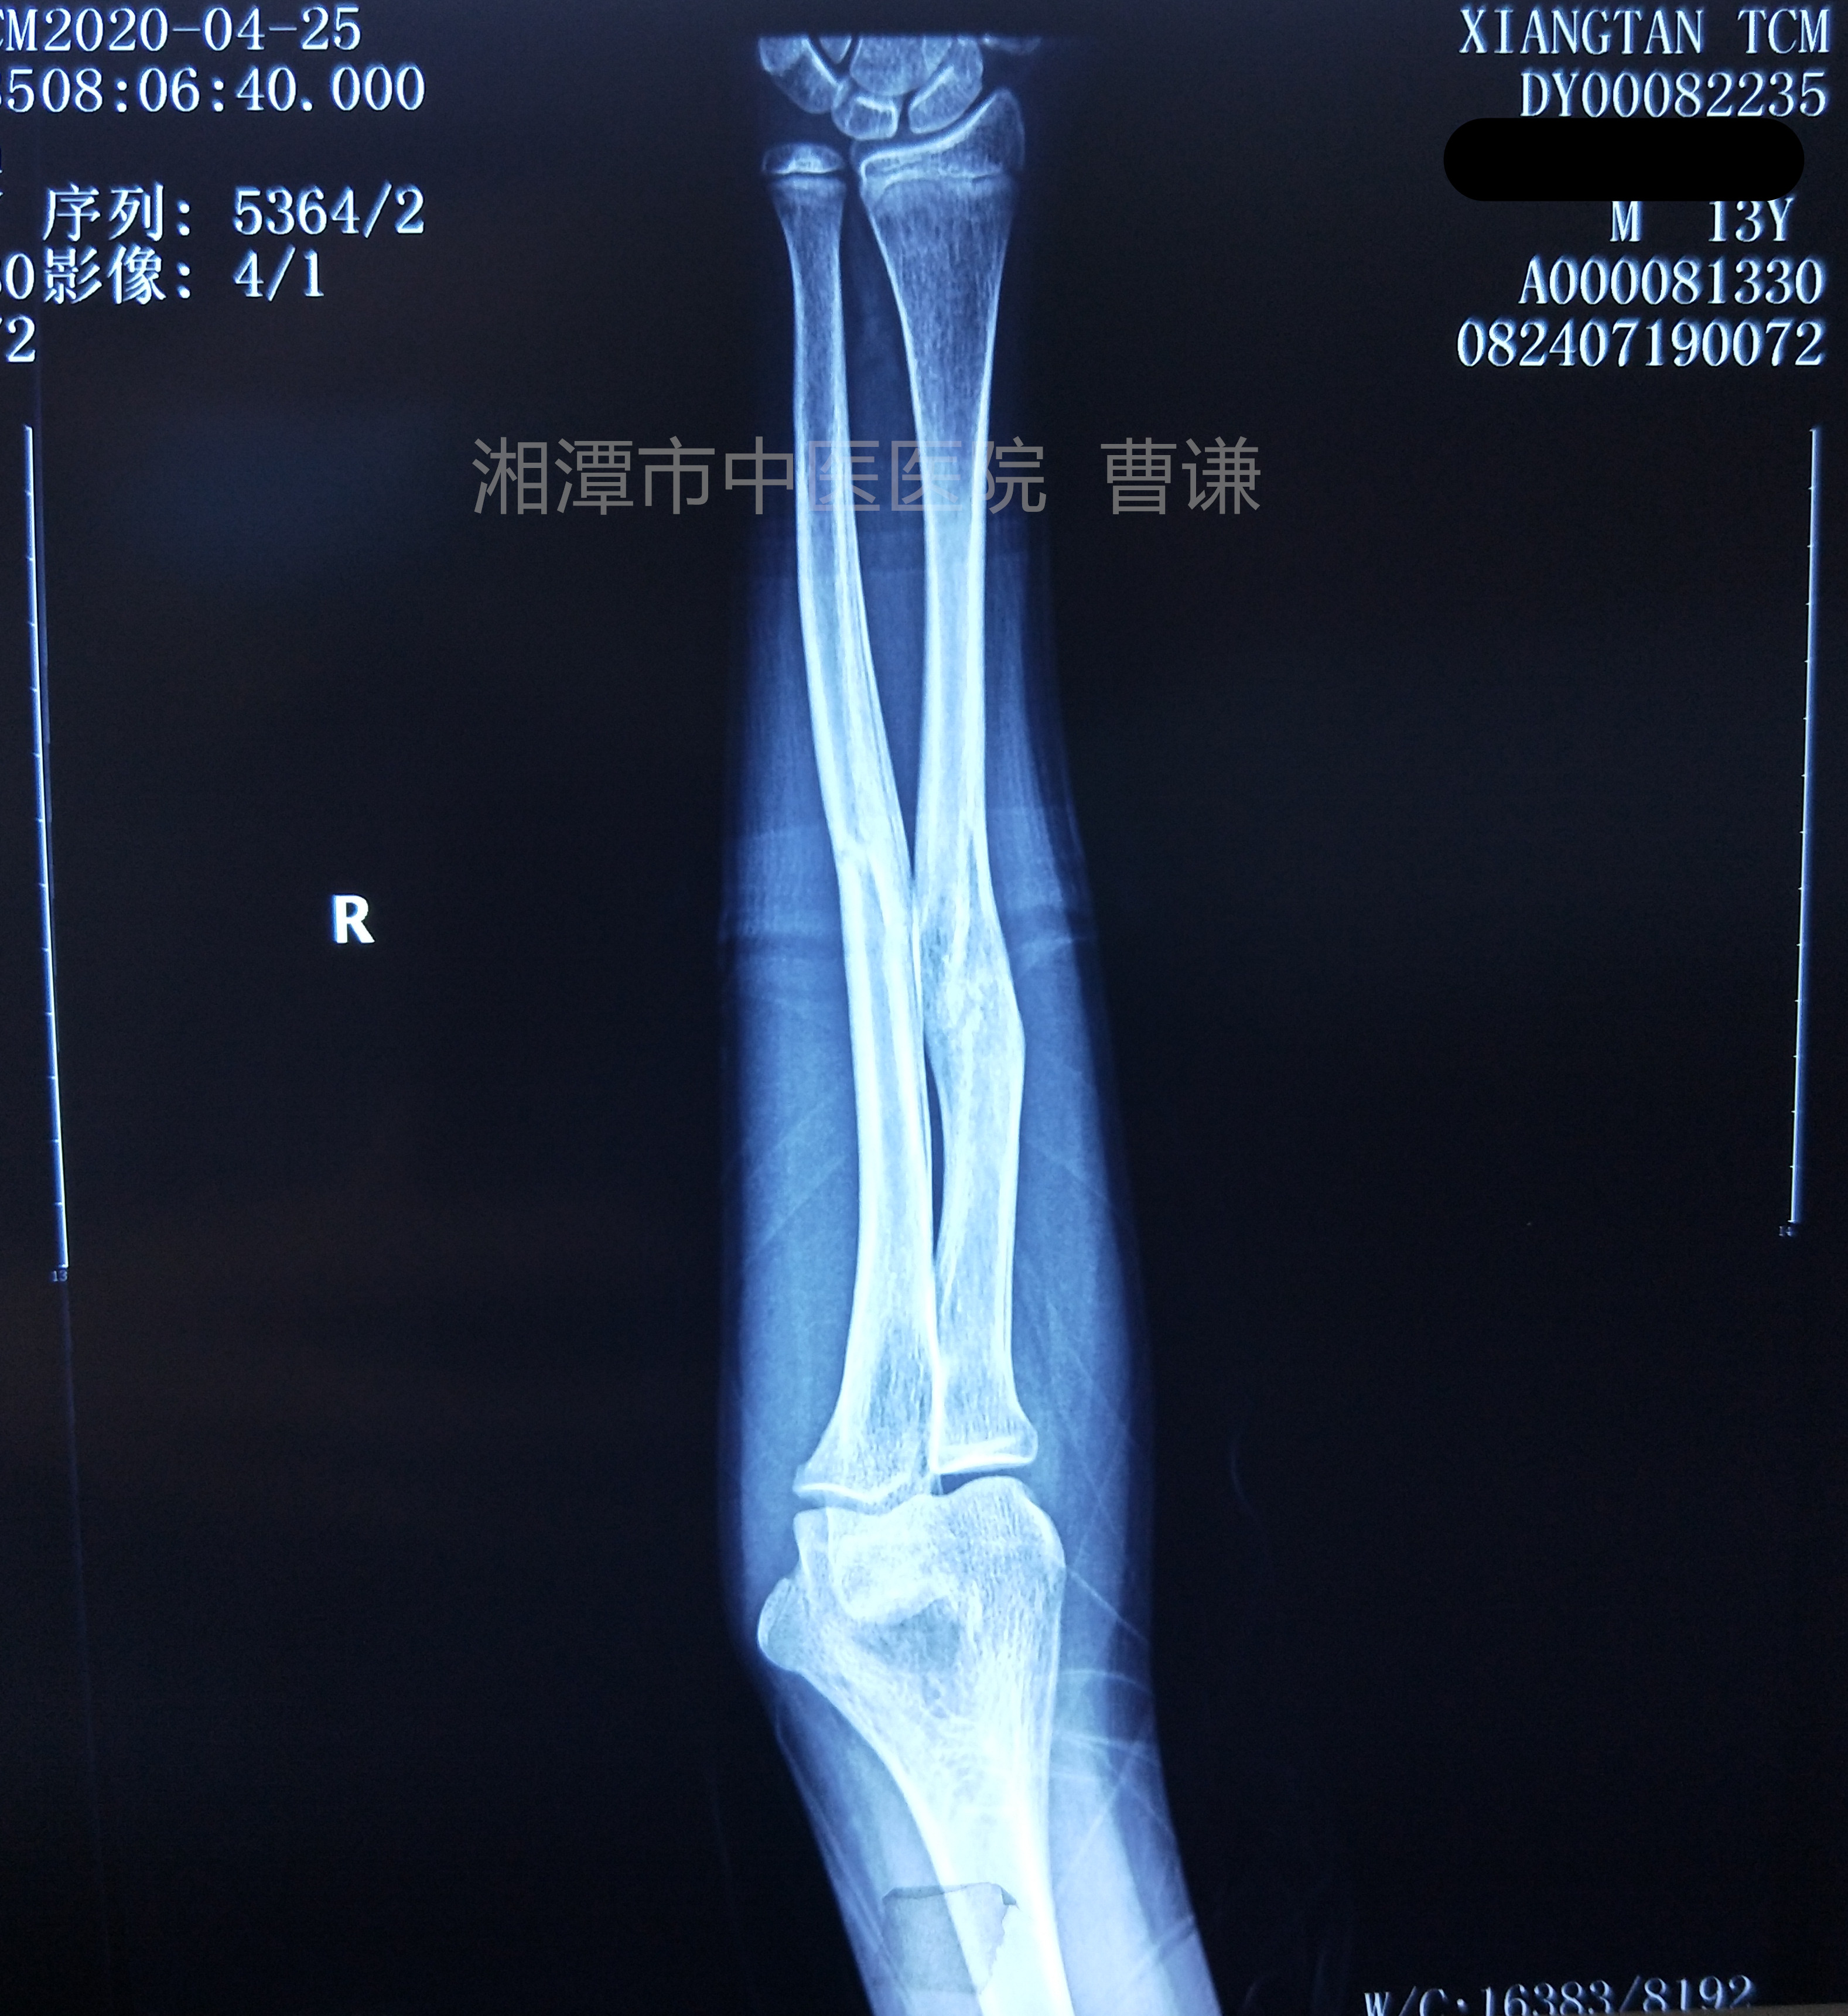

入院后患者家属要求保守治疗,未进行刻意手法整复,采用旋后牵引法进行复位固定,也就是简单的将前臂旋后、在维持牵引的状态下安放夹板,采用四块小夹板及直角托板固定患肢于前臂旋后位屈肘九十度位。具体手法及固定方法请参看http://杨氏旋后牵引法治疗尺桡骨中段骨折之十(附复位固定视频) - 骨科专业讨论版 -丁香园论坛 http://www.dxy.cn/bbs/topic/41778100 帖子中的视频。

固定后拍片复查,是不是觉得比之前的片子对位对线情况更差了?有问题吗?没有问题,可以继续保守治疗!